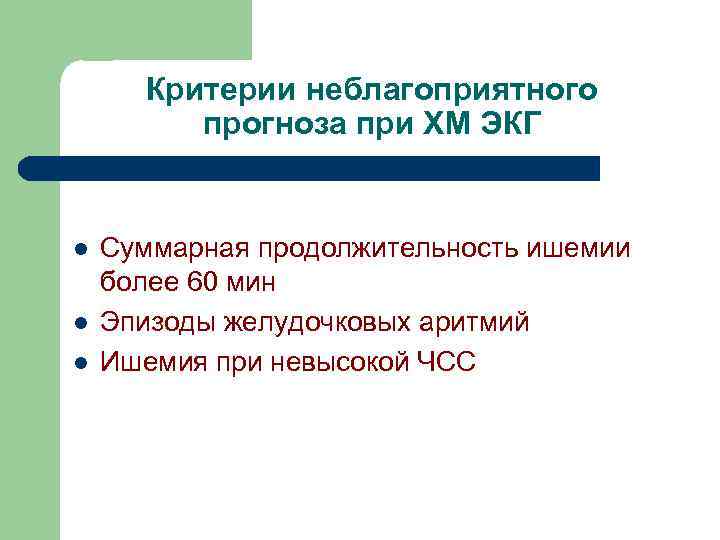

Критерии неблагоприятного прогноза при ХМ ЭКГ l l l Суммарная продолжительность ишемии более 60 мин Эпизоды желудочковых аритмий Ишемия при невысокой ЧСС